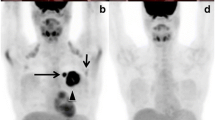

Tumors drain in an orderly manner through the lymphatic system. The SLN is the first to be affected by metastasis if the tumor has spread. A tumor-free SLN makes it highly unlikely for other nodes to be affected. SLN scintigraphy (lymphoscintigraphy) using radiolabeled colloids can accurately localize the sentinel nodes and can show atypical drainage patterns preoperatively (Fig. 6.1). Although lymphoscintigraphy and SLN biopsy (SLNB) have been used to stage many solid cancers, these procedures are most commonly performed in patients with breast cancer and melanoma. In the SLNB procedure, lymphoscintigraphy can improve accuracy, especially in extra-axillary lymph nodes, and can also reduce surgical morbidity [17]. The SPECT/CT procedure may improve the localization of SLNs during the acquisition of lymphoscintigraphy images. Intraoperative detection of SLNs is managed by a gamma probe. Recently, several portable gamma cameras have been developed to provide real-time image guidance for the detection of SLNs during the operation. The most recent developments include the combination of conventional gamma probes with position- and orientation-tracking systems, which permits virtual reconstruction in a three-dimensional environment.

A 52-year-old woman with a newly diagnosed left breast cancer was scanned for preoperative sentinel lymph node evaluation with Tc-99m nanocolloid lymphoscintigraphy. The Tc-99m nanocolloid was injected intramammary in the region of the tumor and periareolar subcutaneously. Dynamic, planar, and SPECT/CT images were recorded after the injections. Planar (c) and SPECT/CT images (a, CT image; b, fusion image; d, SPECT image) showed increased radiotracer uptake in the left axillary lymph node suggestive of the sentinel lymph node. The patient underwent a left mastectomy and left axillary sentinel lymph node biopsy. The surgical pathology report of the left axilla was negative for lymph node metastasis